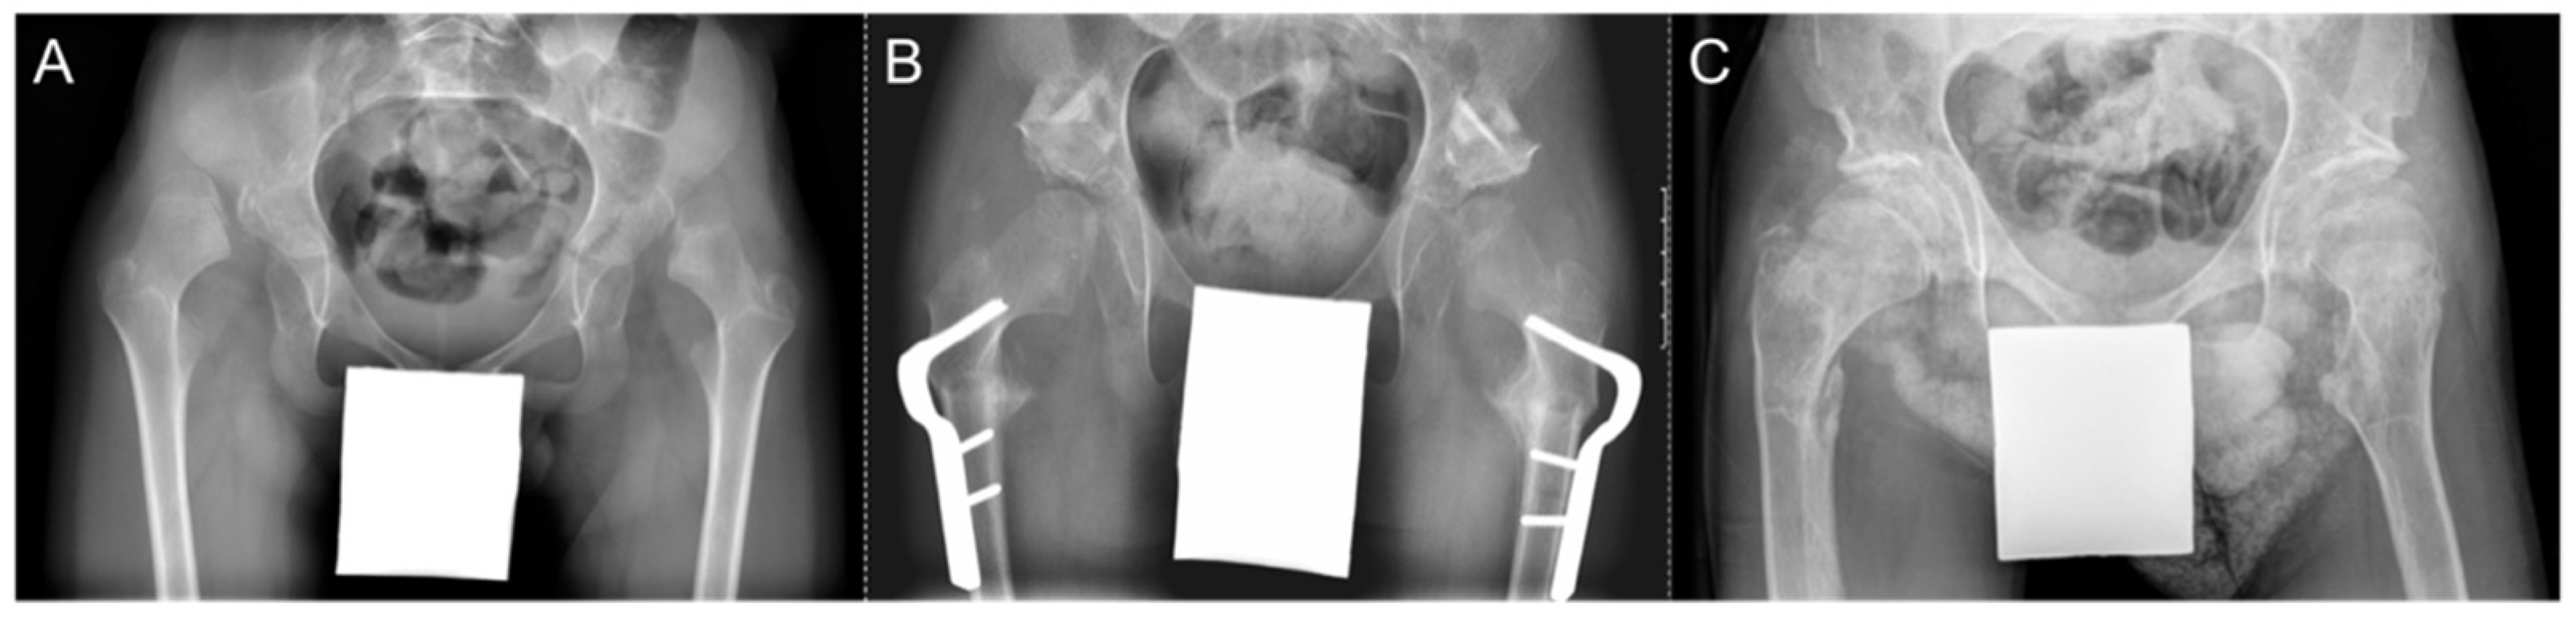

An example of a case of hip reconstruction surgery in a non-ambulatory (GMFCS V), 9-year-old male with bilateral CP is presented in Figure 5. Using the left side as an example, the MP was reduced from 100% to 0% after surgery. The reduction in the hip was maintained 5.5 years post-operatively with an MP of 18%. Prior to surgery, the femoral head had a grade B shape. This remodelled to a grade A shape at the early and late post-operative time points.

Figure 5. Radiographs of a patient with bilateral CP who underwent bilateral hip reconstruction surgery. (A) Pre-operative. (B) Early post-operative. (C) Late post-operative.